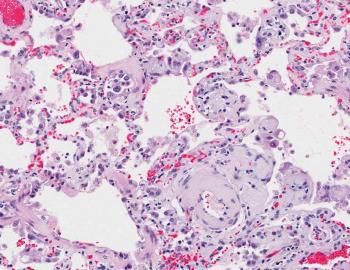

Herkennen van amyloïdose

De diagnose

Cardiale amyloïdose